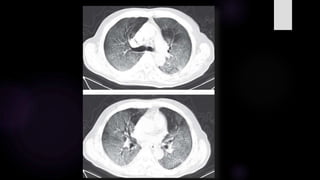

TOMOGRAFIA EN COVID19 SEVERA – CUANTIFICACIÓN DE

SEVERIDAD